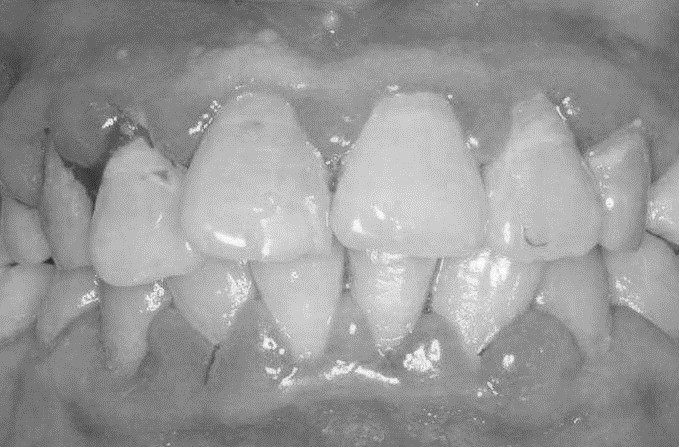

患者,女,52岁。因刷牙出血前来就诊。自述刷牙时牙龈出血2年余,有时吃苹果,馒头等食物时牙龈出血,近1个月早晨起床偶有唾液中带红色血丝。曾作常规血象检查,未见异常。无咬合不适或牙齿松动。检查可见全口牙石(+),有大量菌斑堆积,全口牙龈龈缘中度充血,龈乳头充血肿大,探诊出血明显,但无附着水平丧失,牙齿无松动,咬合关系未见异常。X线片显示全口牙槽骨无明显吸收。检查结果如下图:

全口牙龈龈缘中度充血